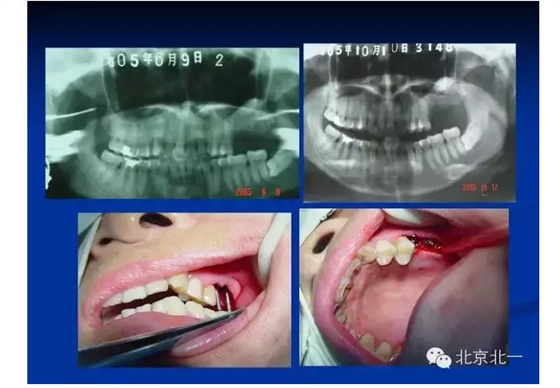

往屆精彩剪影